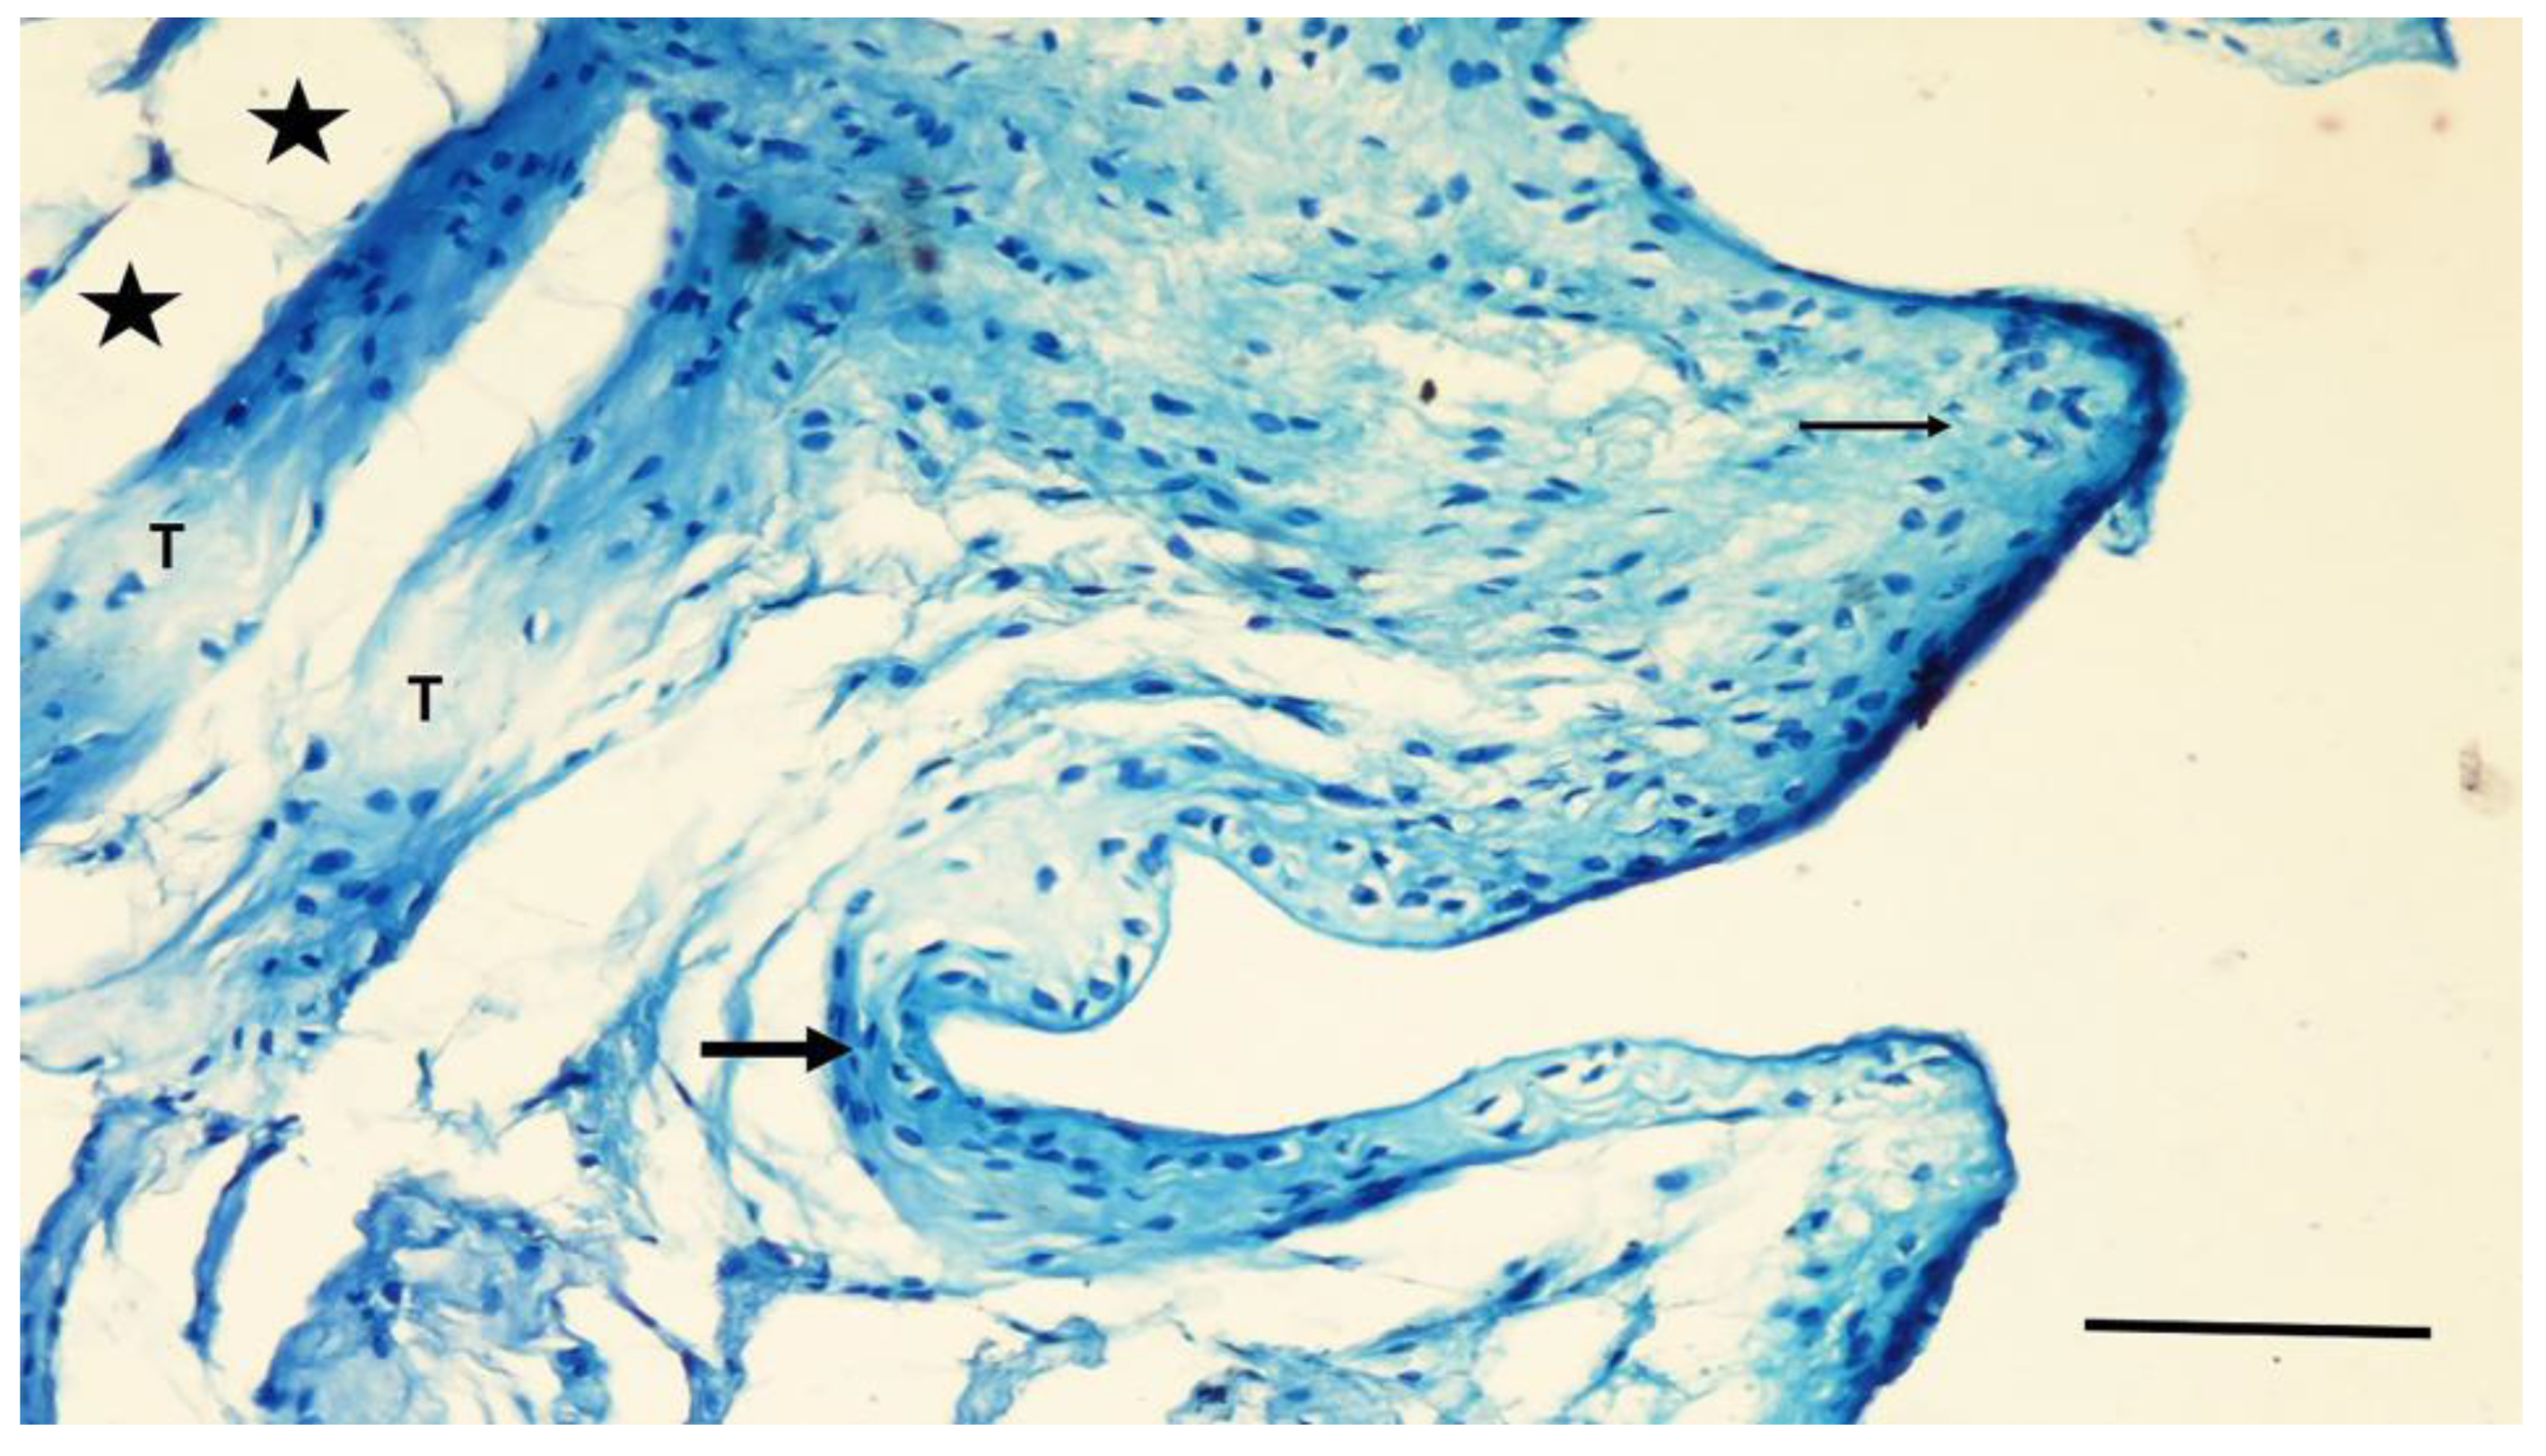

In the PC group, the screw bodies in the cortical region were covered with tissue similar to that in the NC group. The graft particles were partially resorbed in the adjacent defect area, while the smaller particles were highly resorbed. Osteoblastic cells covered the surfaces of the primary bone trabeculae surrounding the particles. In some specimens, a weak infiltration of mononuclear cells was seen in the loose connective tissue between the particles. No giant cells or fibrous capsules were observed around the particles (Figure 7).

Figure 7.

A section through the adjacent defect area of the PC group. Larger Bond Apatite particles (PR) are partially resorbed, while smaller particles are highly resorbed. The particle residues (PR) are surrounded by thin bone trabeculae (T) covered with osteocytes (arrow). Toluidine blue staining. Magnification bar: 100 µm.